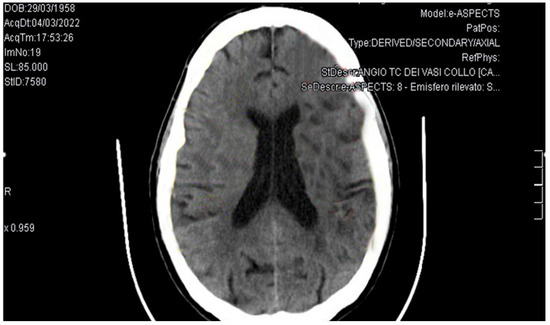

Background and Clinical Significance: Trousseau’s syndrome, characterized by recurrent thromboembolic events and non-bacterial thrombotic endocarditis, represents a severe paraneoplastic condition associated with poor prognosis in cancer patients. Due to the growing life expectancy of cancer patients, Trousseau’s syndrome is becoming more frequent. Consequently, risk of thrombosis and bleeding assessment, as well as early diagnosis and opportune therapy will gain importance. Case Presentation: We describe a case of a 63-year-old Caucasian male presenting with ischemic stroke. During management, he developed a mitral valve marantic endocarditis, and finally the diagnosis of pulmonary adenocarcinoma was performed. The case description is followed by a brief review of the relevant literature on the condition. Discussion and Conclusions: This case highlights the complexity of diagnosing and managing Trousseau’s syndrome. Early recognition, appropriate anticoagulation strategies, and the need for multidisciplinary management are crucial to improve the outcomes and the quality of life for cancer patients. Full article